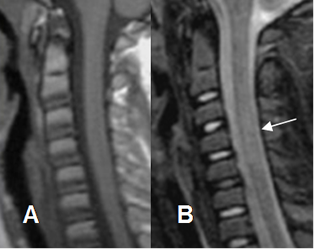

Fig 208 A. Lesión SCIWORA.

A: RM sagital en T1. No se encuentran alteraciones.

B: RM sagital en T2. Sin cambios por fracturas o desalineación. Aumento difuso en la señal de la medula, entre C3 y C5, por edema secundario a lesión SCIWORA.